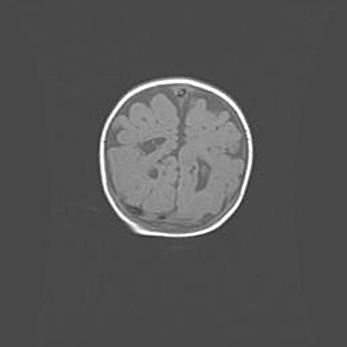

Сообщающаяся гидроцефалия. Кистозная энцефаломаляция головного мозга.

Возраст: 3 месяца 4 дня

Вес: 3100 г

Пол: женский

Окружность головы: 34 см

Срок гестации: 31 неделя

Кистозная энцефаломаляция головного мозга - одна из форм поражения головного мозга в детском возрасте. Характеризуется возникновением множественных и распространённых кист в коре, белом веществе и подкорковых образованиях головного мозга у плодов, новорождённых и детей раннего возраста. Развитие кистозной энцефаломаляции связано с внутриутробной асфиксией и гипотонией, родовой травмой, тромбозом синусов, пороками развития сосудов, инфекциями, сепсисом и другими причинами. Наиболее значимые инфекционные агенты: вирусы простого герпеса, цитомегалии, краснухи, токсоплазмы, энтеробактерии, золотистый стафилококк и другие.